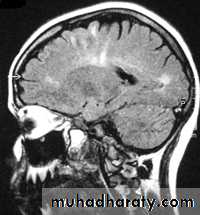

Sagital section of brain ( T1 w post contrast injection)

CORONAL SECTION OF BRAIN ( T1w post contrast injection)